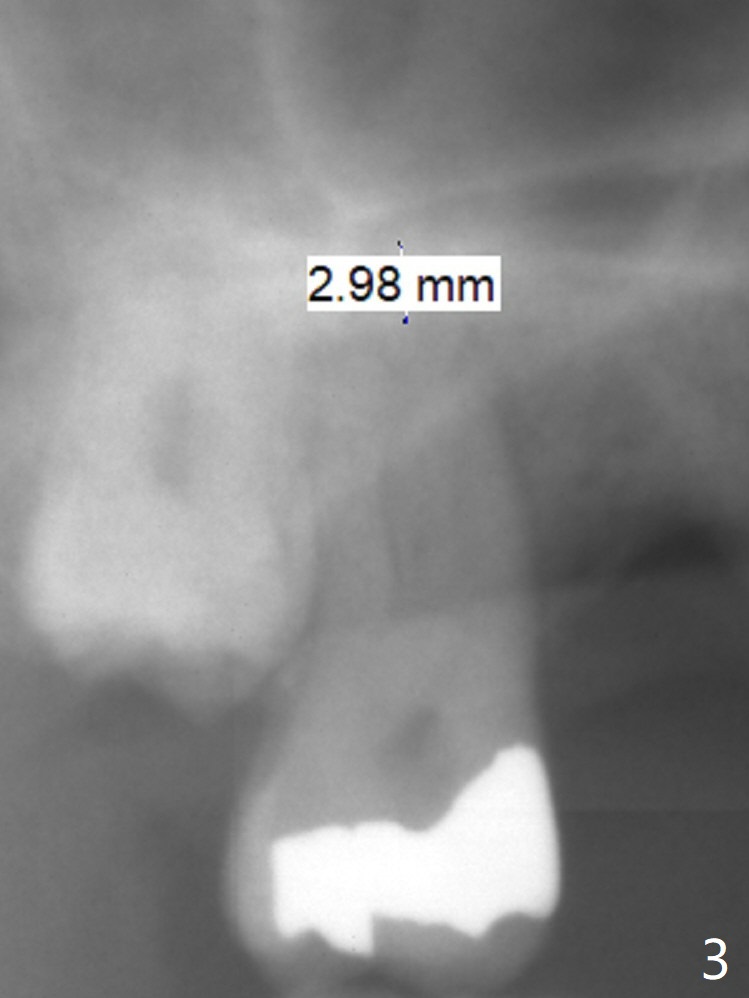

A 58-year-old man had 2 missing molar 3 years ago (Fig.1). Later the tooth #2 fractures with apparently severe bone loss (Fig.2). If the septum is lost, bone height is around 3 mm (Fig.3). Take PA before using Magic Sinus Lifter. Since his bone density is high, increase exposure time. If the septum is present (Fig.4), use Magic Drills sequentially (1.6, 2.8, 3.2 mm ....). PRF plug and membrane (1 each) are to be prepared.